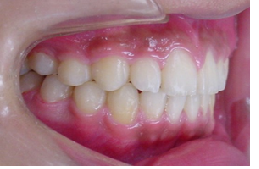

当矯正歯科医院ではMEAW法(マルチループ)で治療する事で非抜歯で治療しています。

MEAW法(マルチループ)を利用することで以下の様に上顎前突が改善されていきます。

初診時

治療途中

終了時